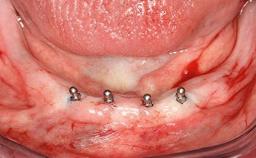

Early Implant Placement with GBR using DBBM

Early (Type 2) placement in a healthy, non-smoking male patient aged 28 years who required removal and replacement of the maxillary right central incisor due to external root resorption. A horizontal bone deficit requires a simultaneous augmentation procedure. The overall esthetic risk is high due to the horizontal bone deficit, medium to high lip line with exposure of the soft tissue margin when smiling, and the patient’s high esthetic expectations.

After flapless tooth extraction and a healing period of 6 weeks, a standard-diameter one-piece implant is placed. A gap between the implant and the facial bone wall is filled with autogenous bone chips harvested from the anterior nasal spine and covered with DBBM particles. Contour augmentation on the facial aspect is achieved using DBBM particles and a collagen membrane, according to the principles of guided bone regeneration (GBR). The flap is coronally repositioned for semisubmerged healing.